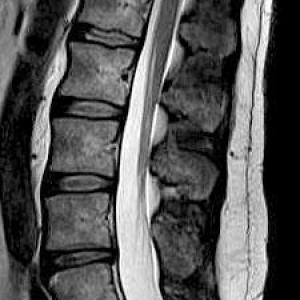

Die Kernspintomographie liefert detailgenaue Schnittbildaufnahmen des menschlichen Körpers ohne Röntgenstrahlen – und das sogar von Blutgefäßen. Bei der MRT werden Sie in einem starken Magnetfeld untersucht. Ähnlich wie bei einem Radio werden UKW-Wellen verwendet. Um dünne Schichtaufnahmen zu erzeugen, benötigen wir zusätzlich schwach wechselnde Magnetfelder, wodurch ein lautes Klopfgeräusch entsteht. Die Signale werden dann von einem sehr leistungsfähigen Computersystem zu Schichtaufnahmen in verschiedenen Ebenen umgewandelt. Die Untersuchung dauert je nach Fragestellung 7 bis 35 Minuten. Während der Messzeit sollten Sie ruhig und entspannt liegen, denn jede Bewegung verursacht Bildstörungen und verlängert die Prozedur.